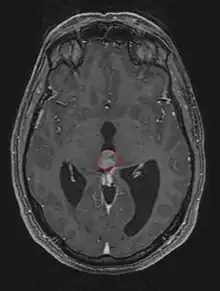

Frequently, paralysis of upward gaze along with several ocular findings such as convergence retraction nystagmus and eyelid retraction also known as Collier's sign and Light Near Dissociation (pupil accommodates but doesn't react to light) are known collectively as Parinaud's syndrome[1] or Dorsal Mid-brain syndrome, are the only physical symptoms seen. This is caused by the compression of the vertical gaze center in the midbrain tectum at the level of the superior colliculus and cranial nerve III. Work-up usually includes Neuro-imaging as seen on the right.